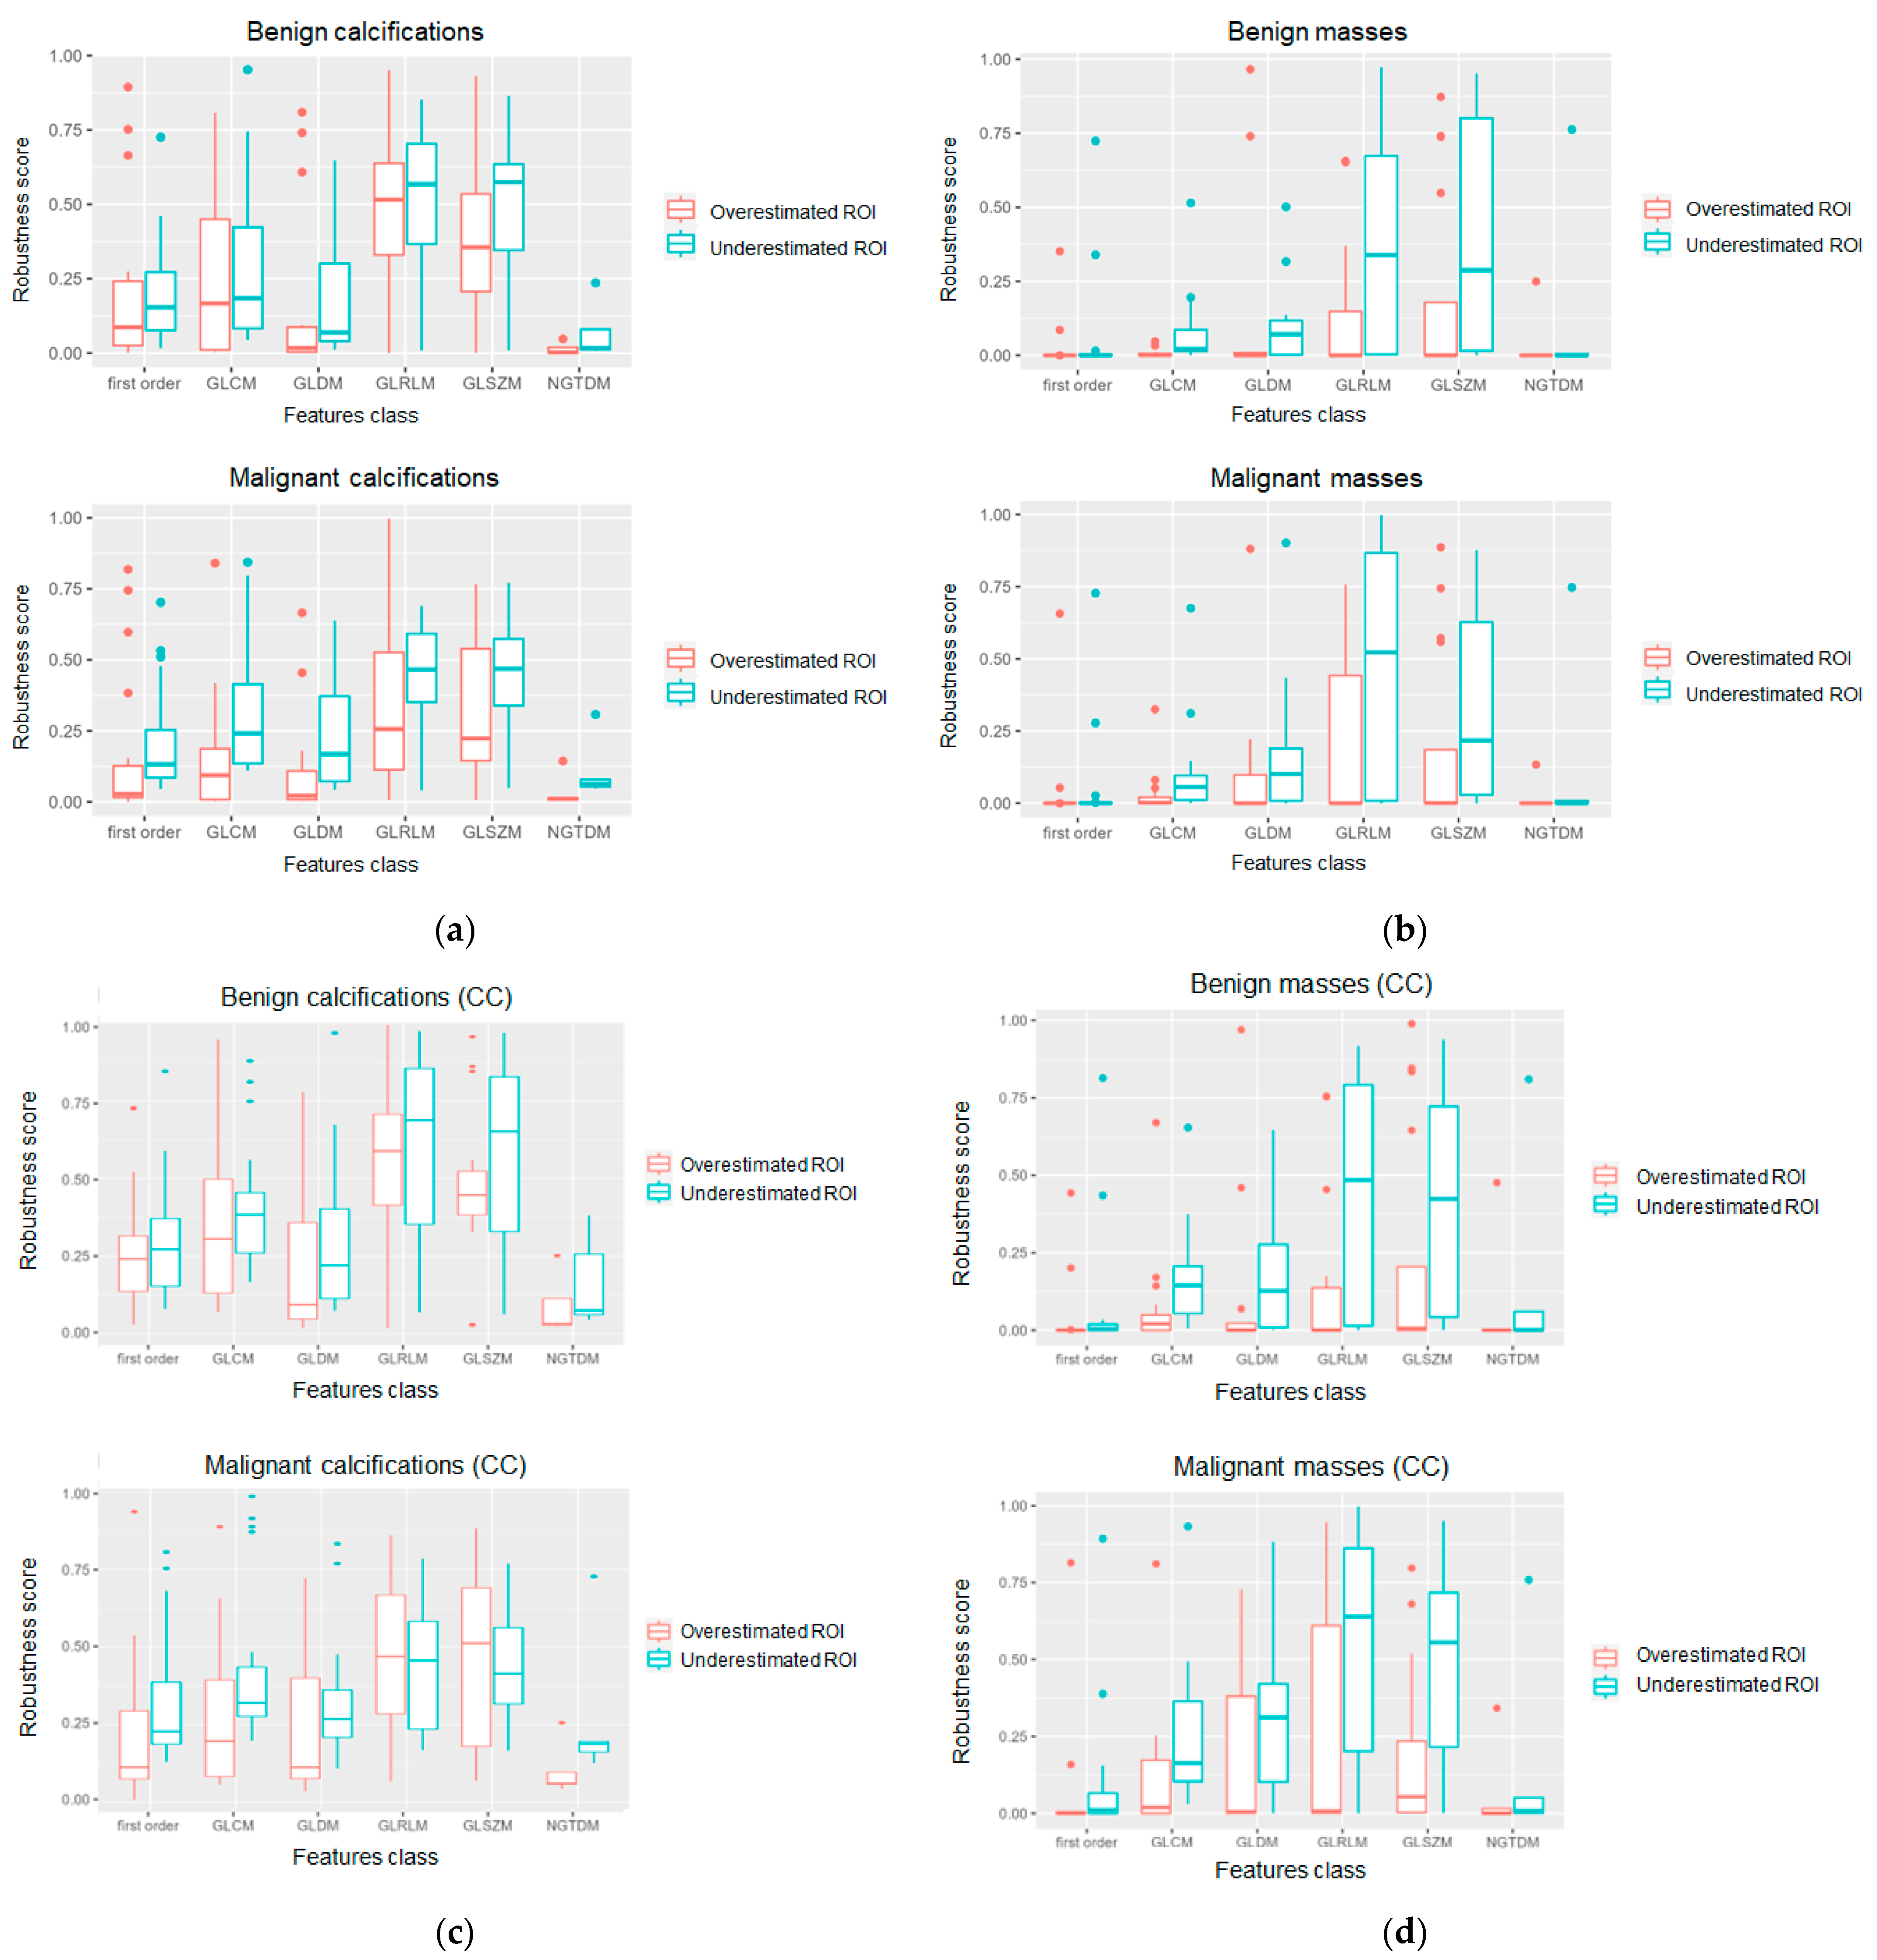

3. Results

4. Discussion